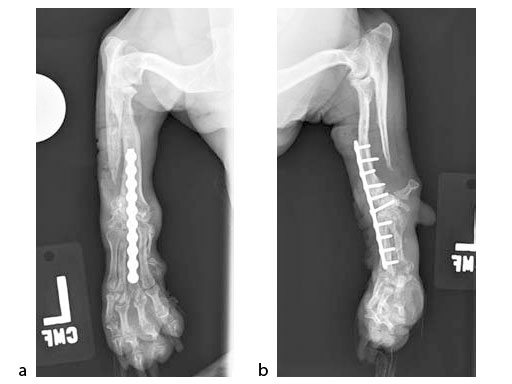

A 5-year-old female 3.5 kg dachshund with bilateral carpal hyperextension secondary to erosive polyarthroplathy (rheumatoid arthritis) (Fig 3, Fig 4) was treated bilaterally with a staged pancarpal arthrodesis with straight LCPs. The right carpus was operated first and healed in 10 weeks. The left carpus was operated 5 months after the initial surgery (Fig 5). Complete healing was noted 3 months postoperatively (Fig 6).

At the most recent follow-up 20 months postoperatively (first arthrodesis), the dog was comfortable and very active. The plates were selected based on the small bone size and the risk of secondary osteopenia. Locking screws are important to prevent screw loosening in patients with poor bone quality, especially in the case of pancarpal arthrodesis where high bending forces must be neutralized.